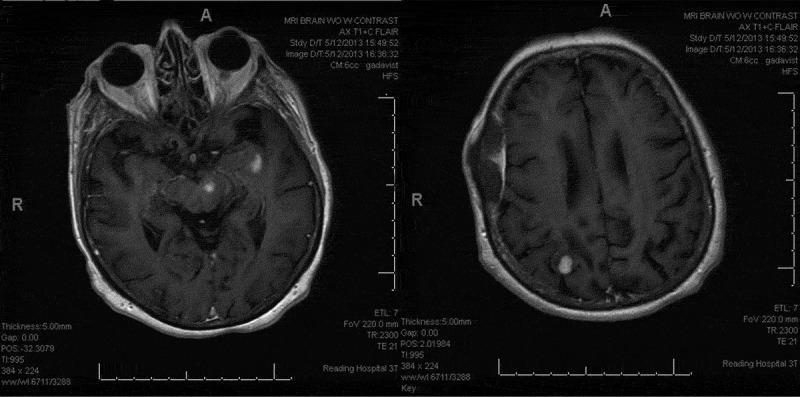

Introduction Mycophenolate Mofetil (MMF), although a widely used immunosuppressant; an increasing concern of MMF induced Primary Central Nervous System Lymphoma (PCNSL) are being reported. Timely diagnosis and management of MMF induced PCNSL can play a vital role in improved outcomes. Case Presentation Eighty-one-year-old female with history of Eosinophilic Granulomatosis with Polyangiitis (EGPA) presented with word finding difficulty, right-hand weakness and right foot clumsiness. EGPA had been stable with MMF for 6 years. Physical examination revealed weakened right-hand grip, positive right-sided dysdiadokokinesia and right foot drop. MRI-brain identified three enhancing solid lesions - in right parietal, left insular and left mid brain extending into the left thalamus. Brain biopsy revealed a focally dense lymphoid infiltrate with CD20 positive B cells, with large atypical cells resembling Hodgkin Reed-Sternberg cells. With concern for immunosuppression related PCNSL, MMF was stopped. Patient was treated with 8 weeks of rituximab therapy for its least toxic profile and concomitant benefit in EGPA. On a 2 month follow up MRI-brain, near total resolution of the intracranial lesion was observed. Patient still had some residual right lower extremity incoordination, however, strength and speech normalized with resolution of dysdiadokokinesia. Patient was advised to discontinue MMF indefinitely and remains on low dose prednisone daily. Conclusion MMF is an inhibitor of Inosine Monophosphate Dehydrogenase which prevents T- and B-cell proliferation. PCNSL is a potential complication of chronic immunosuppression with this medication. Discontinuation of the drug along with immunosuppressive therapies have been the effective therapeutic options till date.

引言 霉酚酸酯(MMF)虽是一种广泛使用的免疫抑制剂,但关于MMF诱发原发性中枢神经系统淋巴瘤(PCNSL)的报道日益增多。及时诊断和处理MMF诱发的PCNSL对改善预后起着至关重要的作用。病例报告 一名81岁女性,有嗜酸性肉芽肿性多血管炎(EGPA)病史,出现找词困难、右手无力和右脚笨拙。EGPA在使用MMF治疗6年期间病情稳定。体格检查发现右手握力减弱、右侧轮替运动障碍阳性和右脚下垂。脑部MRI检查发现右侧顶叶、左侧岛叶和左侧中脑有三个强化实性病变,并延伸至左侧丘脑。脑活检显示有局灶性密集的淋巴细胞浸润,CD20阳性B细胞,并有类似霍奇金里德-施特恩贝格细胞的大的非典型细胞。鉴于担心与免疫抑制相关的PCNSL,停用了MMF。患者接受了8周的利妥昔单抗治疗,因其毒性最小且对EGPA有协同益处。在2个月后的脑部MRI随访中,观察到颅内病变几乎完全消退。患者仍有一些右下肢共济失调的残留症状,然而,随着轮替运动障碍的消退,肌力和言语功能恢复正常。建议患者无限期停用MMF,并继续每日服用低剂量泼尼松。结论 MMF是肌苷单磷酸脱氢酶的抑制剂,可阻止T细胞和B细胞增殖。PCNSL是这种药物慢性免疫抑制的潜在并发症。迄今为止,停用该药物并结合免疫抑制治疗一直是有效的治疗选择。